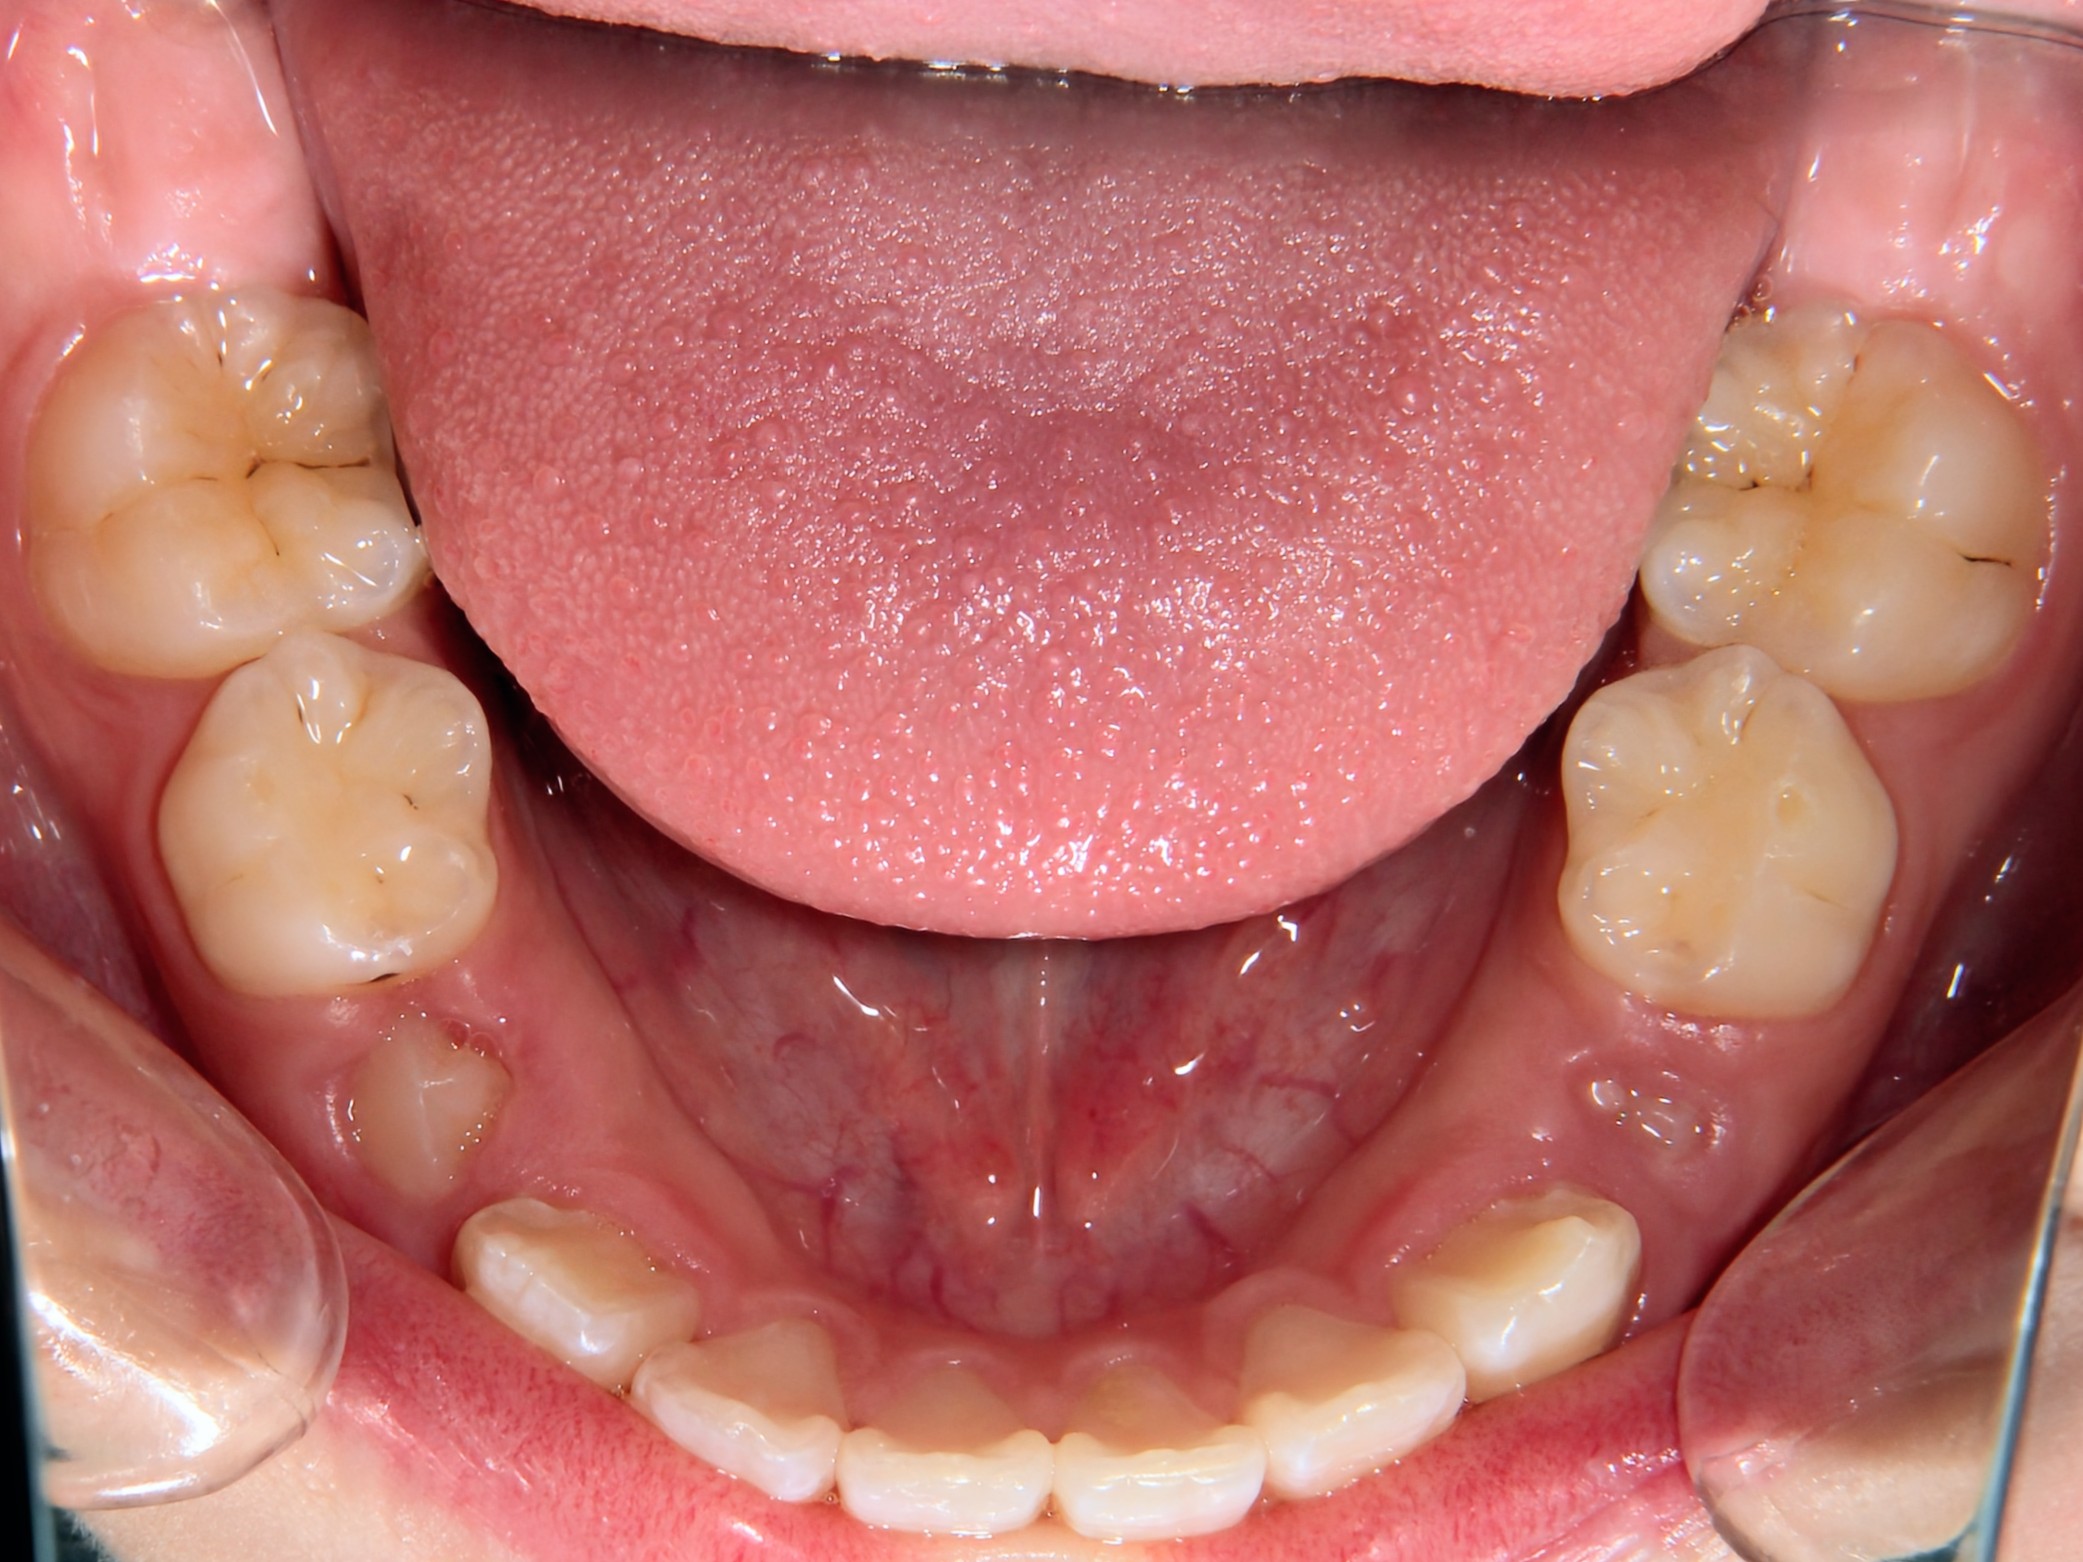

第2期治療終了時

口腔内写真

治療結果

上下の歯のデコボコが改善

全体的な咬み合わせの緊密化

治療費(調整料含めて)

約95万円(第1期治療…40万円、第2期治療…55万円)

第1期治療期間

第1期治療開始:2021年8月

第1期治療終了:2022年1月

動的治療期間:5か月

第2期治療期間

第2期治療開始:2024年9月

第2期治療終了:2025年7月

動的治療期間:10か月

合計期間

3年10か月(動的治療期間:1年3か月+経過観察期間:2年7か月)

患者様は歯のデコボコを主訴で来院しましたが、第1期治療で歯列拡大+前歯部矯正を行ったことで、第2期治療で非抜歯矯正にて治療終了することができました。